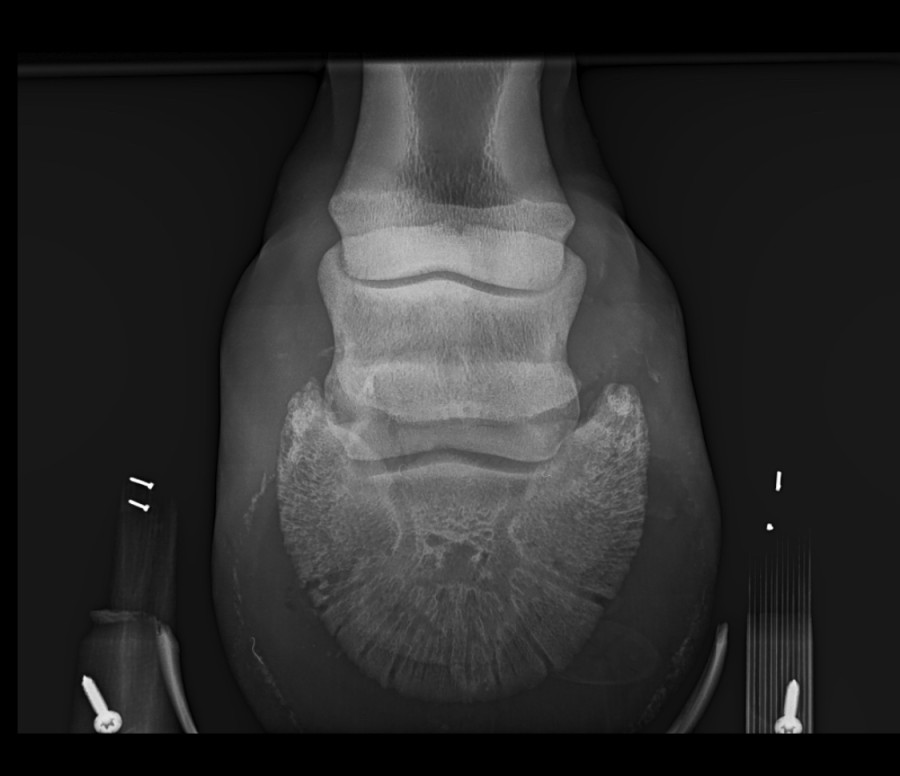

Le cheval de mon copain boite depuis qq temps. On a d'abord pensé à un abcès mais cela a duré et le véto après radios a posé un diagnostic de sclérose de l'os sous chondral proximal p2.

D'après lui ce défaut de congruence de l'articulation P1-P2 entraine une inflammation sous chondrale de P2.

Voilà les radios

Le cheval est pieds nus et l a tjrs été.

On peut voir quoi exactement sur les radios??

quanele non . . . C'est le compte rendu écrit de la même véto. Il n'est plus question d ?dème. Je ne comprends pas ! Je ne sais pas ce que l'on voit à la radio. A la consultation ce n'était pas l articulation p1-p2 qui semblait poser souci mais celle du dessus . . .